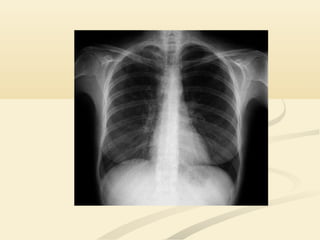

 Si parte del pulmón es radiodensa esto puede afectar aSi parte del pulmón es radiodensa esto puede afectar a

nuestra capacidad para ver las estructuras adyacentes.nuestra capacidad para ver las estructuras adyacentes.

 Estudiaremos como la patología de diferentes lóbulos yEstudiaremos como la patología de diferentes lóbulos y

segmentos afecta al aspecto de los órganos contiguossegmentos afecta al aspecto de los órganos contiguos..

 Dos sustancias de la misma densidad, en contactoDos sustancias de la misma densidad, en contacto

directo, no se diferencian entre sí en una radiografía.directo, no se diferencian entre sí en una radiografía.

 Este fenómeno, la perdida de la silueta (el contorno)Este fenómeno, la perdida de la silueta (el contorno)

radiográfica normal, se denominaradiográfica normal, se denomina SIGNO DE LASIGNO DE LA

SILUETASILUETA..